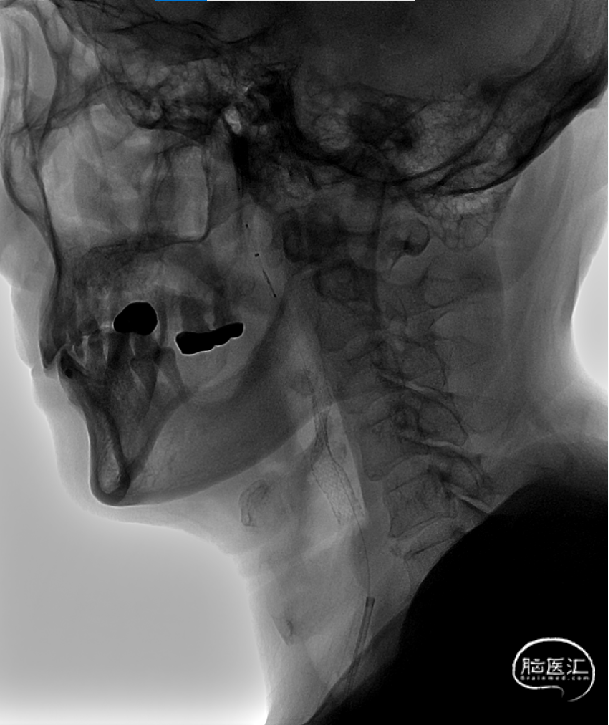

回收保护伞:

经保护伞导丝送入保护伞回收鞘,小心回收及撤出保护伞,保护伞内未见小碎屑。

操作要点:回收鞘沿保护伞导丝送入时避免刮支架,如不能顺利送入常规操作可使患者向对侧转头或按压颈部。Safecer栓塞保护器拥有市面唯一可塑形保护鞘,预先小角度塑性,可大大提高回收鞘到位性。

术后侧位造影:

术后正位造影: